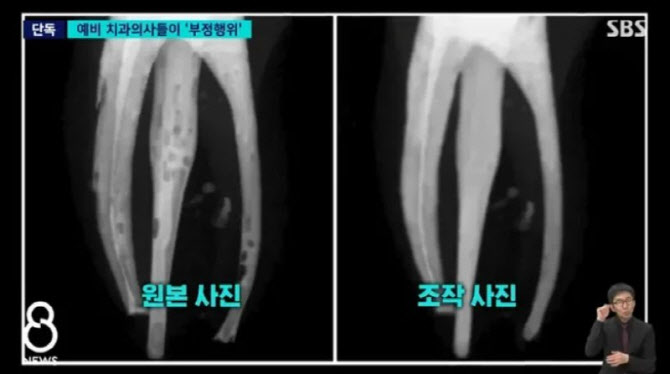

'포토샵 쓱싹' 연세대 치대생들...실습 치료 결과 조작